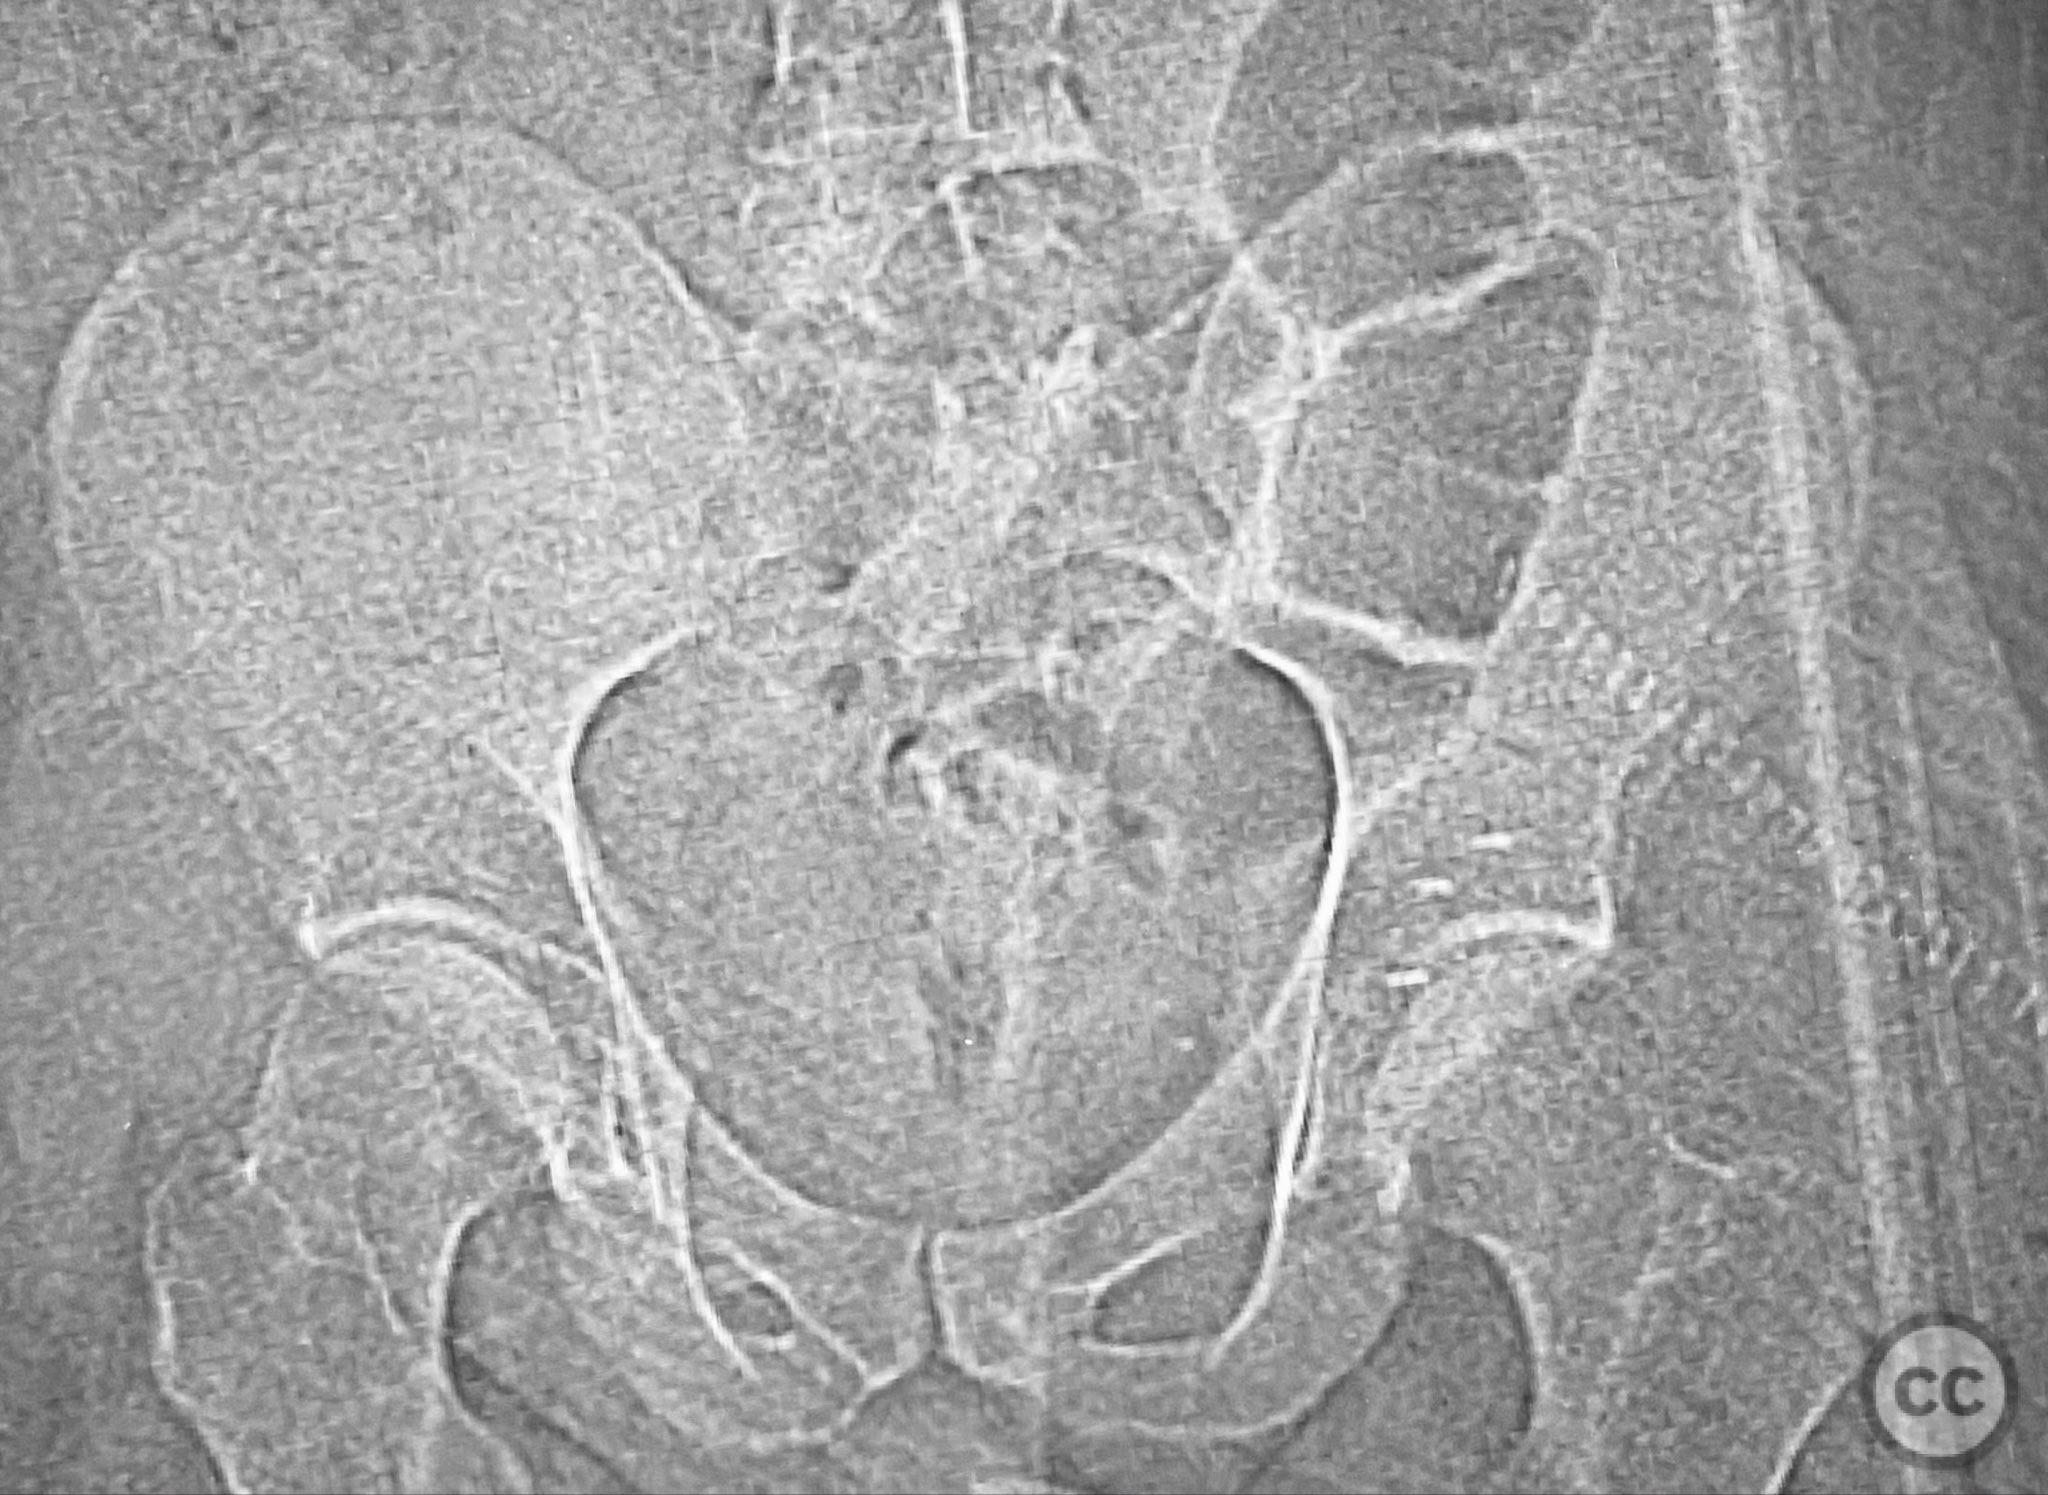

Clinical and radiological findings:  A patient involved in a motor vehicle collision presented with left hip pain exacerbated by any attempted movement. Initial axial and surface-rendered computed tomography (CT) imaging demonstrated an essentially nondisplaced posterior wall (PW) acetabular fracture (AO/OTA 62-A1.1). However, the anteroposterior (AP) scan image and coronal reconstructions revealed significant hip joint asymmetry. Examination under anesthesia with fluoroscopic guidance confirmed persistent joint incongruity, with the femoral head subluxating posteriorly at 50–60 degrees of flexion. A pure chondral fragment was identified as being interposed between the femoral head and the intact region of the posterior wall, accounting for the clinical and radiological asymmetry.